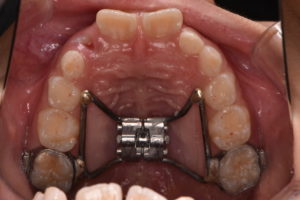

Ⅰ期治療として上顎には急速拡大装置、下顎にはバイヘリックスを用いることで狭窄歯列の拡大を行い、前歯部のスペース不足の改善を行った後に、マルチブラケットを併用することで歯列の配列を行った。前歯部の配列終了後舌側に保定ワイヤーで歯牙の固定を図り治療終了となった。